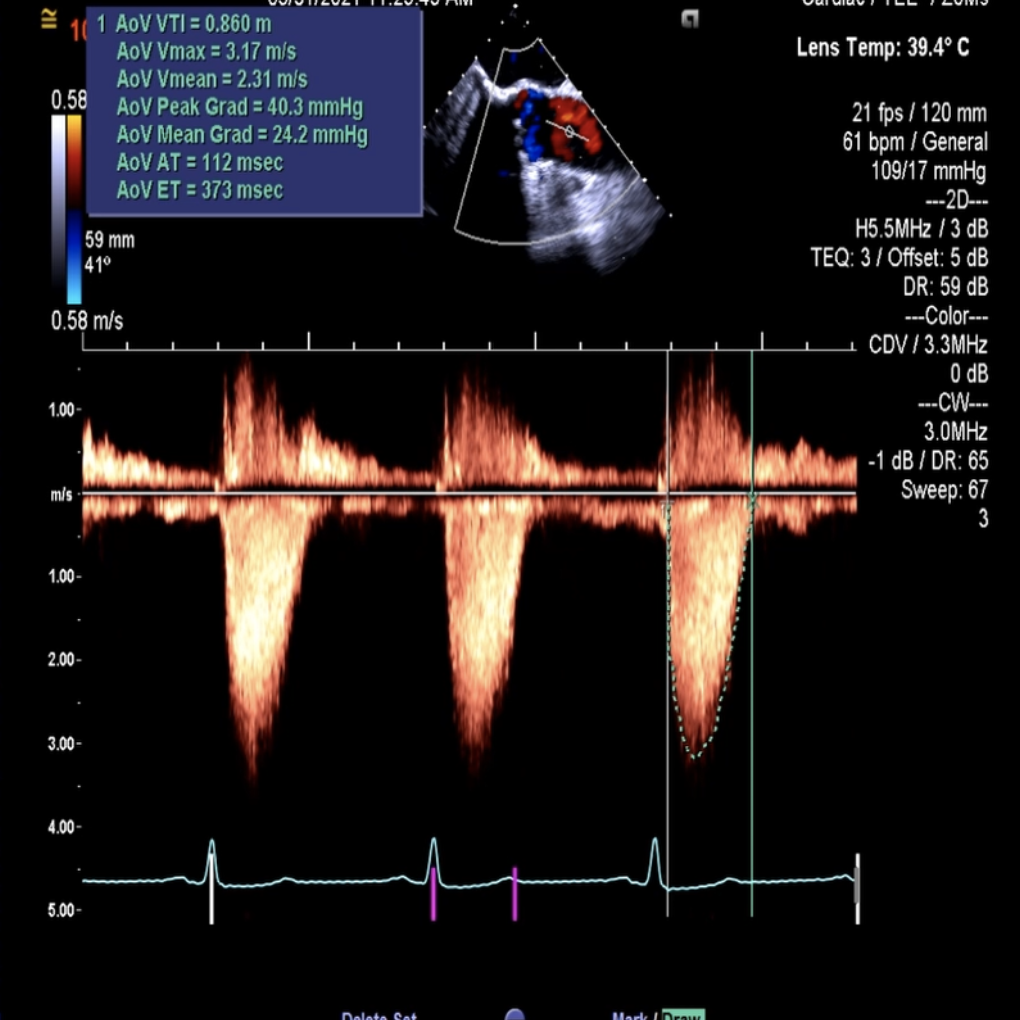

术前术后超声对比

术后超声评估影像,平均压差2.8mmHg,最大流速1m/s,无反流